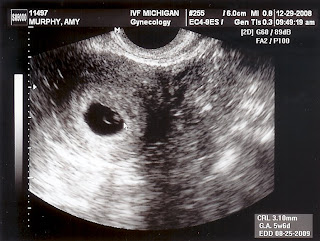

I am so thankful to be seven weeks pregnant today...

We have an ultrasound tomorrow at 3pm and I am on pins and needles. I hope this baby is growing and developing. I feel pretty good with few symptoms. Honestly, I think my symptoms could perhaps even be more in my head than actual. I still have tender breasts and I have to urinate quite frequently, but other than that things seem pretty normal. I also have small bouts with constipation and fatigue and a tiny bit of nausea. I

almost wish I felt like shit because I would be more assured that I was indeed pregnant. It just doesn't seem real yet.